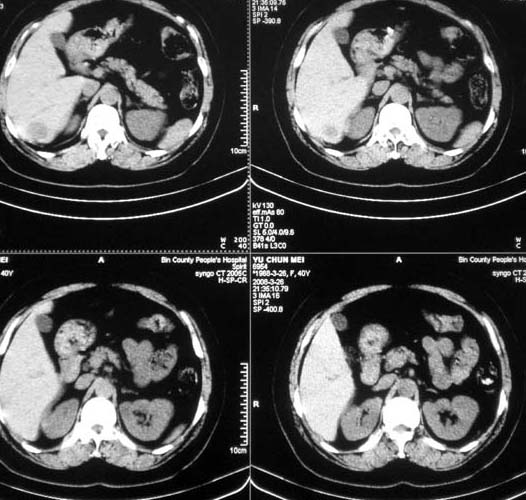

肝脏血管瘤.境界清楚,以前已确诊,没有必要增强吧?

多发性血管瘤!

仍然考虑肝血管瘤

肝内多发低密度影,边缘清楚,结合病史考虑:肝血管瘤可能性大,建议必须时增强扫描。

平扫不敢诊断血管瘤。